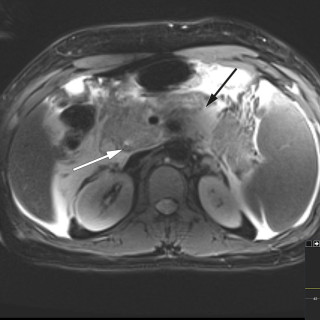

En mann i 50-årene ble innlagt etter residiverende episoder med brystsmerter. På innleggelsesdagen synkoperte han fra sittende stilling. Utredningsforløpet avdekket en diagnose som er sjelden, men med klassiske symptomer og funn. En mann i 50-årene med kjent hypertensjon, velregulert med kandesartan (tabletter, 8 mg × 1), ble henvist til akuttmottaket på grunn av episoder med brystsmerter. Han var normalvektig, hadde aldri røykt og hadde ingen rusbrukslidelse, og det var ingen kjent diabetes, hyperkolesterolemi, opphopning av hjertesykdom eller prematur hjertedød i familien. Over en periode på...